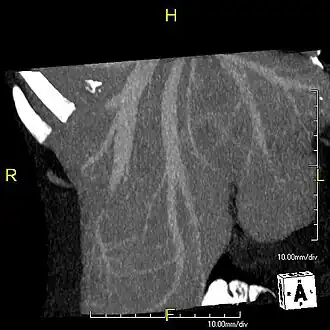

-

Axial CT image showing anomalous hepatic veins coursing on the liver's subcapsular anterior surface[74] -

Maximum intensity projection (MIP) CT image as viewed anteriorly showing the anomalous hepatic veins coursing on the anterior surface of the liver -

Lateral MIP view in the same patient as previous image -

A CT scan in which the liver and portal vein are shown